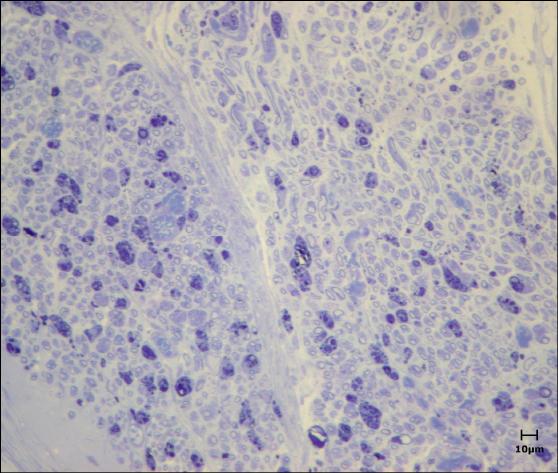

(Fig.1).

FIGURA 1: Animal na mesa operatória para cirurgia em nervo facial esquerdo.